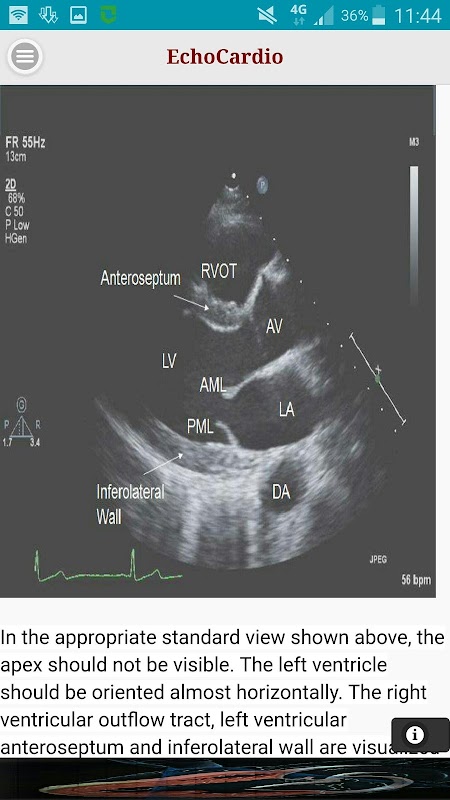

Parasternal Long Axis

Transthoracic echocardiography (TTE) adalah pemeriksaan ultrasound jantung yang paling biasa dilakukan. A berkualiti tinggi transthoracic ekokardiogram boleh dilakukan dengan cepat di sisi katil itu dan mempunyai potensi untuk menilai secara menyeluruh kiri dan kanan sistolik ventrikel dan fungsi diastolik, gerakan dinding serantau, penyakit jantung injap, dan penyakit perikardium.